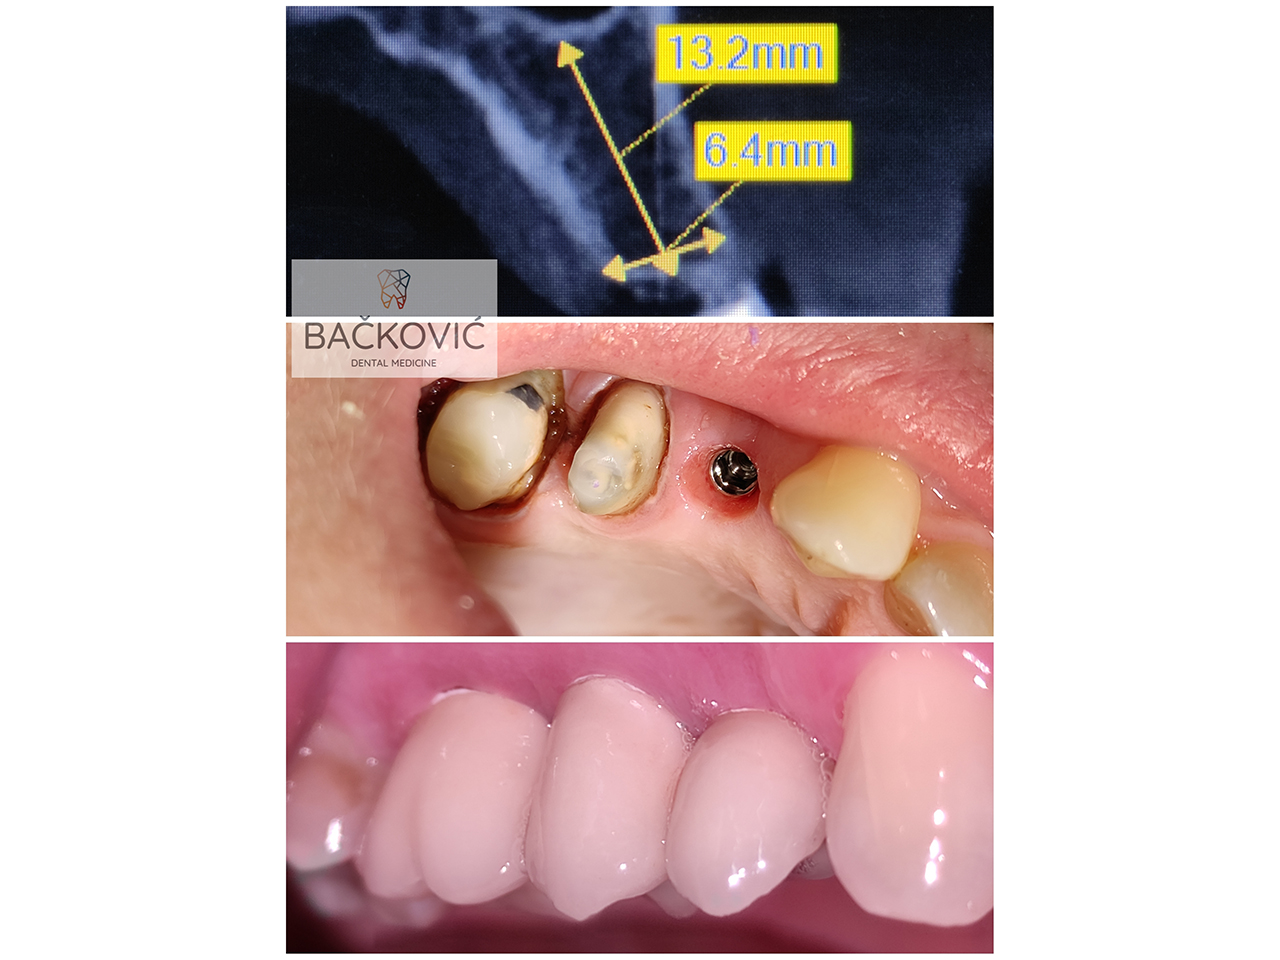

• ИМПЛАНТОЛОГИЯ (установка дентальных имплантатов и искусственной кости, All-on-4, синус-лифтинг, PRF и др.)

• ПРОТЕЗИРОВАНИЕ (коронки и мосты, безметалловая керамика, протезы и др.)

Наша команда состоит из профессиональных специалистов и экспертов в различных областях стоматологии и медицины, получивших образование в Университете Белграда. Благодаря постоянному профессиональному совершенствованию мы можем предложить вам наиболее качественные терапевтические решения. В повседневной работе мы используем новейшие методы и современные стоматологические материалы известных мировых производителей. Устанавливаемые нами дентальные имплантаты относятся к числу самых качественных и известных премиальных систем. Особое внимание уделяется строгому протоколу стерилизации инструментов, а также мерам биологической защиты от Covid-19.